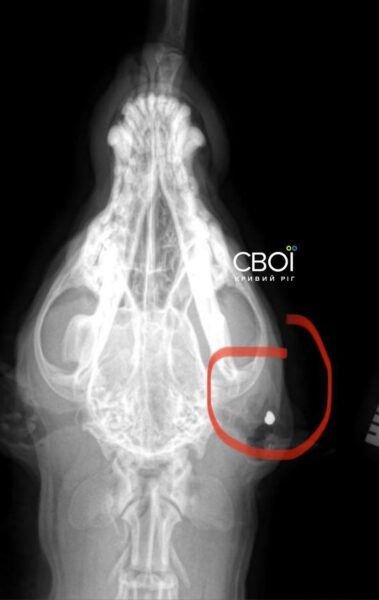

Ветеринар призначив лікування для Баті. Одна з куль застрягла у голові тварини, інша – біля шлунка. Дістати їх, аби не нашкодити собаці, неможливо.